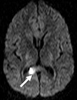

Ce patient de 32 ans présente un malaise brutal, alors qu’il travaille sur son ordinateur. Il décrit une vision brouillée, puis une sensation de chaleur et tombe de sa chaise. Il ne perd pas conscience et est relevé par ses collègues après quelques minutes.

Il est emmené aux urgences. Une IRM est réalisée à la recherche en particulier d’une lésion vasculaire. Sur l’IRM, on met en évidence des hypersignaux FLAIR de la substance blanche périventriculaire et sous-corticale, dont l’aspect est évocateur de